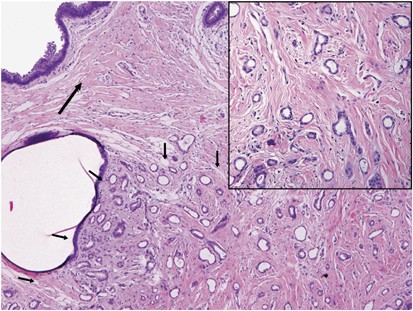

In one patient, the sonography revealed a solid asymmetric density measuring 4.0 cm. in greatest dimension with a 1.4 cm hypoechoic area within this lesion that was suspicious for malignancy on imaging. Core needle biopsy specimen of suspicious hypoechoic irregular area revealed invasive ductal carcinoma, however no obvious changes of pseudoangiomatous stromal hyperplasia were noted (Figure 3, inset). Only upon examination of the entire lesion on excisional specimen, it became obvious that invasive carcinoma (0.9 cm in greatest dimension) was entirely confined to and occupied approximately up to one-third of the underlying pseudoangiomatous stromal hyperplasia tumor that was grossly well demarcated and measured 4.0 cm in greatest dimension (Figure 3).

Invasive ductal carcinoma (short arrows) partially involves pseudoangiomatous stromal hyperplasia tumor (long arrow) (hematoxylin and eosin stain, original magnification × 40). Pseudoangiomatous stromal hyperplasia changes in stroma of invasive tumor on core needle biopsy specimen were not so conspicuous (inset), and final diagnosis of underlying pseudoangiomatous stromal hyperplasia tumor was made only upon excision (hematoxylin and eosin stain, original magnification × 100).